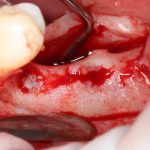

Рекомендации по установке имплантов. Для всех. Часть V.